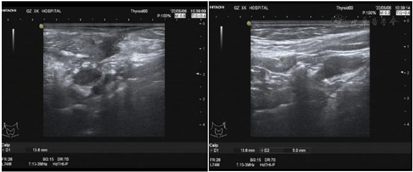

实验室提示白细胞(WBC)16.33×109/L,中性粒细胞比率(NE%)76.7 %,血红蛋白(HGB) 105 g/L,嗜酸性粒性粒细胞0.89×109/L。抗IFN-γ抗体滴度治疗期间三次复查均高于1:100。血T-SPOT试验结果为不确定。HIV(-)。痰涂片找分枝杆菌×3次阴性。右侧颈部淋巴结活检病理高通量宏基因测序检测见波斯分枝杆菌属,序列数352;痰及右侧颈部淋巴结活检组织培养及鉴定提示堪萨斯分枝杆菌生长;右侧锁骨上淋巴结脓液病理高通量测序检测见马尔尼菲蓝状菌感染,序列5149;支冲液高通量测序检测见马尔尼菲蓝状菌,序列1。2022年1月19日右侧颈部淋巴结病理提示其内见胶原纤维及纤维母细胞增生,个别可疑形成不良的上皮样细胞、组织细胞、中性粒细胞、淋巴细胞及浆细胞浸润。抗酸染色见个别阳性杆菌,六胺银、Warthin-Starry及PAS染色(-)(图1)。双侧颈部淋巴结彩色超声(图2、图3);胸部CT(图4、5)。

患者于入院后22 d出院,其后规范服药,2个月后复查痰、支冲液及右侧颈部淋巴结穿刺组织培养分枝杆菌、真菌、致病菌均阴性。4个月后追踪复查彩超、胸部CT提示右侧颈部、锁骨上、纵隔淋巴结均好转、缩小。